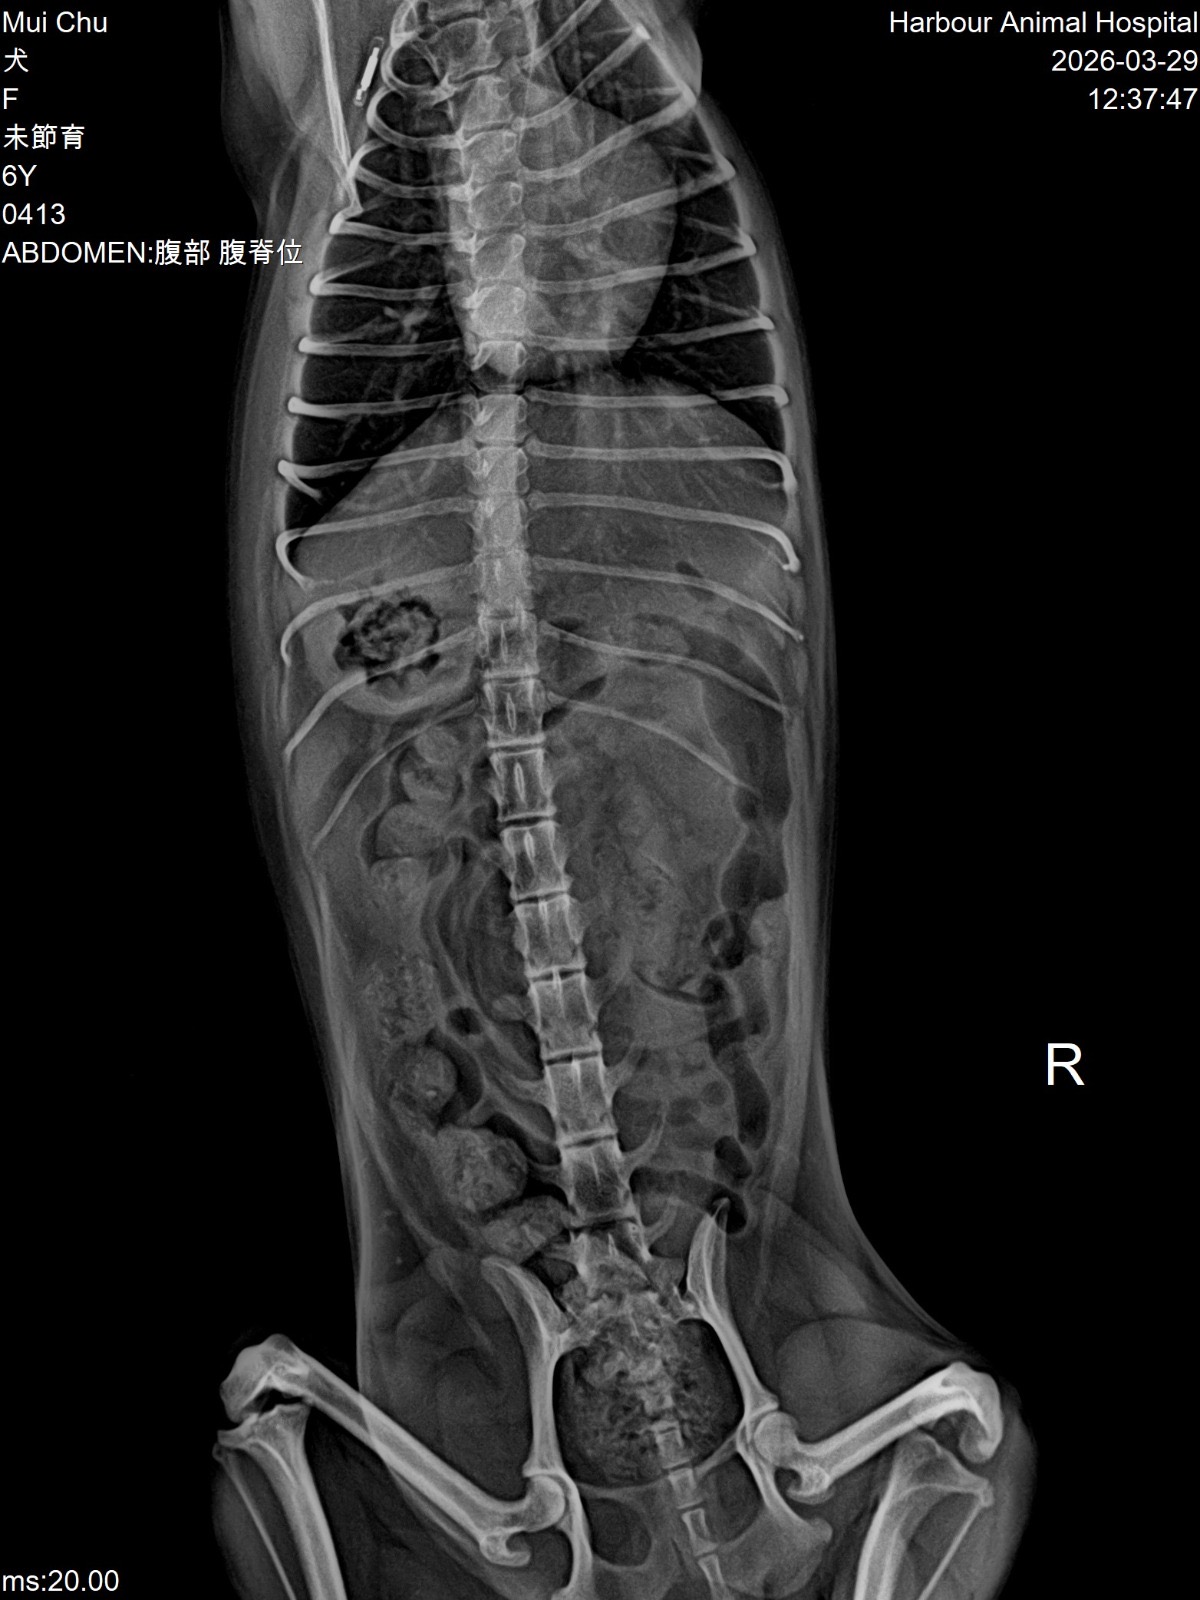

妹豬睇醫生 Get link Facebook X Pinterest Email Other Apps March 29, 2026 由於妹豬忍尿問題已有一段時日,星期六帶妹豬的尿去驗,夜間獲通知有晶石,所以星期日需帶妹豬去檢查!蔽日帶妹豬去診所照X光,萬幸無結石,只需食藥,但將來要留意骨刺的問題 Get link Facebook X Pinterest Email Other Apps Comments